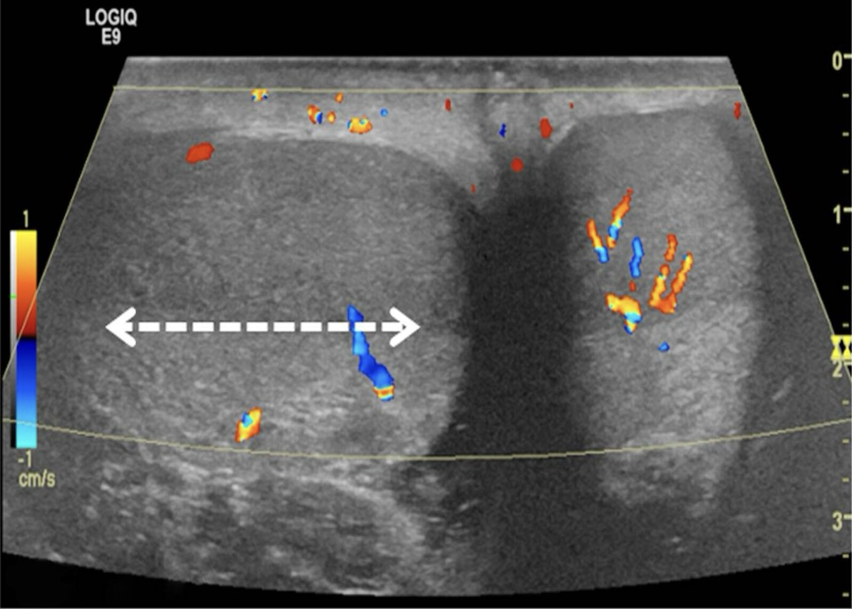

Color Doppler ultrasound of both testes (transverse plane) of a 14-year-old boy who woke up with acute right scrotal pain

The right testis lies in an abnormal horizontal position (white arrow), with intratesticular flow slightly reduced compared to the left testis. These findings are consistent with testicular torsion.